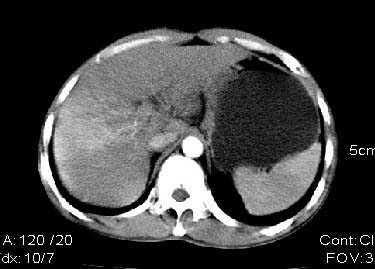

男:42岁。反复恶心呕吐半年。b超:右肝内多发占位,胆石胆囊炎.胆总管扩张

本例特点动脉期右叶近肝门区可见高密度强化,后段也见早期强化,静脉期肝门区高密度区造影剂退出,余密度均匀,考虑肝癌伴动静脉漏,肝右叶上段可见扩张胆管,考虑由于肿瘤压迫胆管引起阻塞,

考虑较典型的肝癌并提示肝门淋巴结肿大。